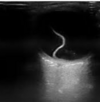

Que estudio es y que se puede ver

USG que muestra retina doblada y brillante

29

¿De qué enfermedad sospechas?

Desprendimiento de retina